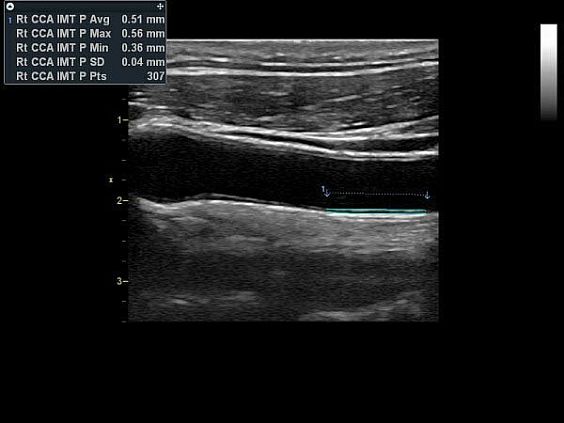

- Опция оценки толщины комплкса интима-медия (IMT)

- Auto IMT — инструмент для автоматического определения границ и толщины комплекса интима-медиа и проведения необходимых расчетов.